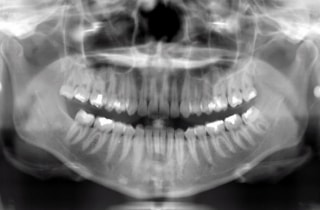

デジタルレントゲン

患者様に負担をかけず、現状を詳しく把握すること。

超高感度だから被曝量が軽減され、お子様にも優しいレントゲン。

当院のデジタルレントゲンは、従来のフィルムを使用したレントゲン撮影に比べ、人体に受ける放射線の量を、約1/4~1/10に抑える事が可能です。

照射時間が短縮され、より低線量でのレントゲン画像取得が可能となります。

お子様にも安心です。